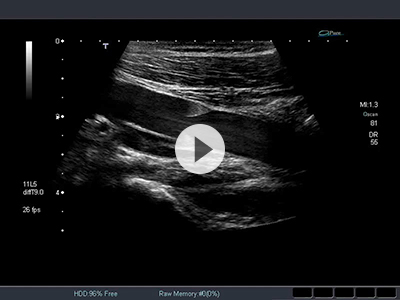

血栓の超音波画像 膝窩部、圧迫操作 動画ライブラリ。

4-1web10 膝窩動脈の描出動画ライブラリ。